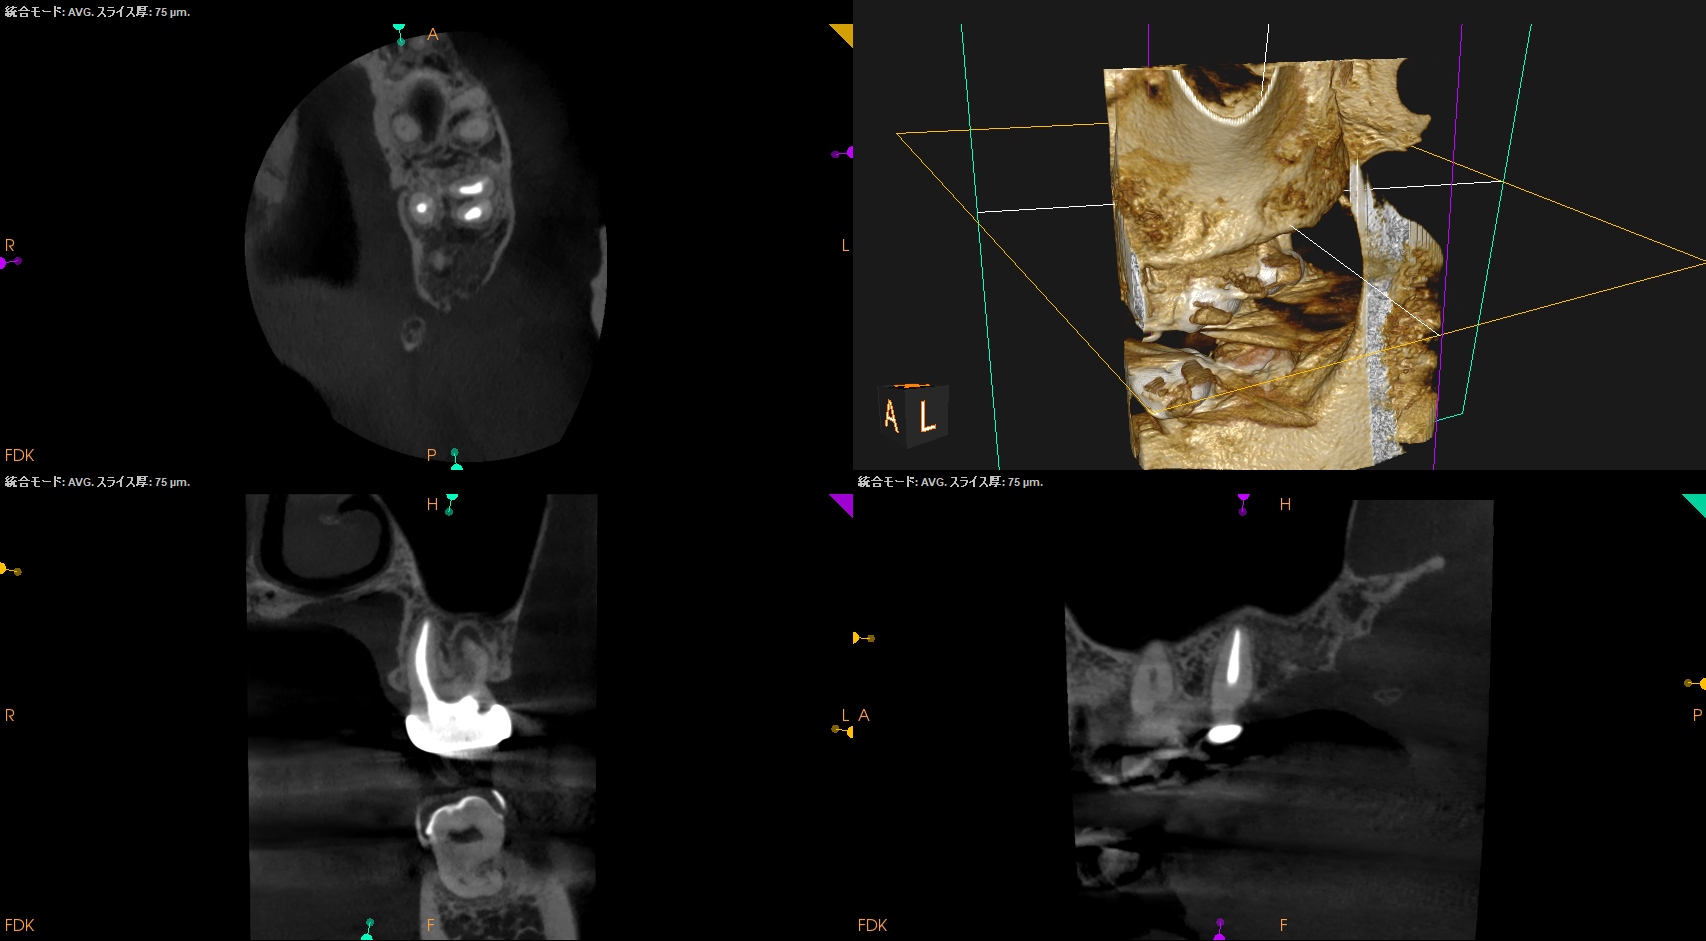

左上7番のMB,DBをApicoectomyしたと言う珍しい?ケースだ。

#15 MB,DB Apicoectomy 1yr recall(2026.1.15)

術前の根尖病変、術直後の歯槽骨の欠損は完治した。

ということで経過観察もこの日で終了した。